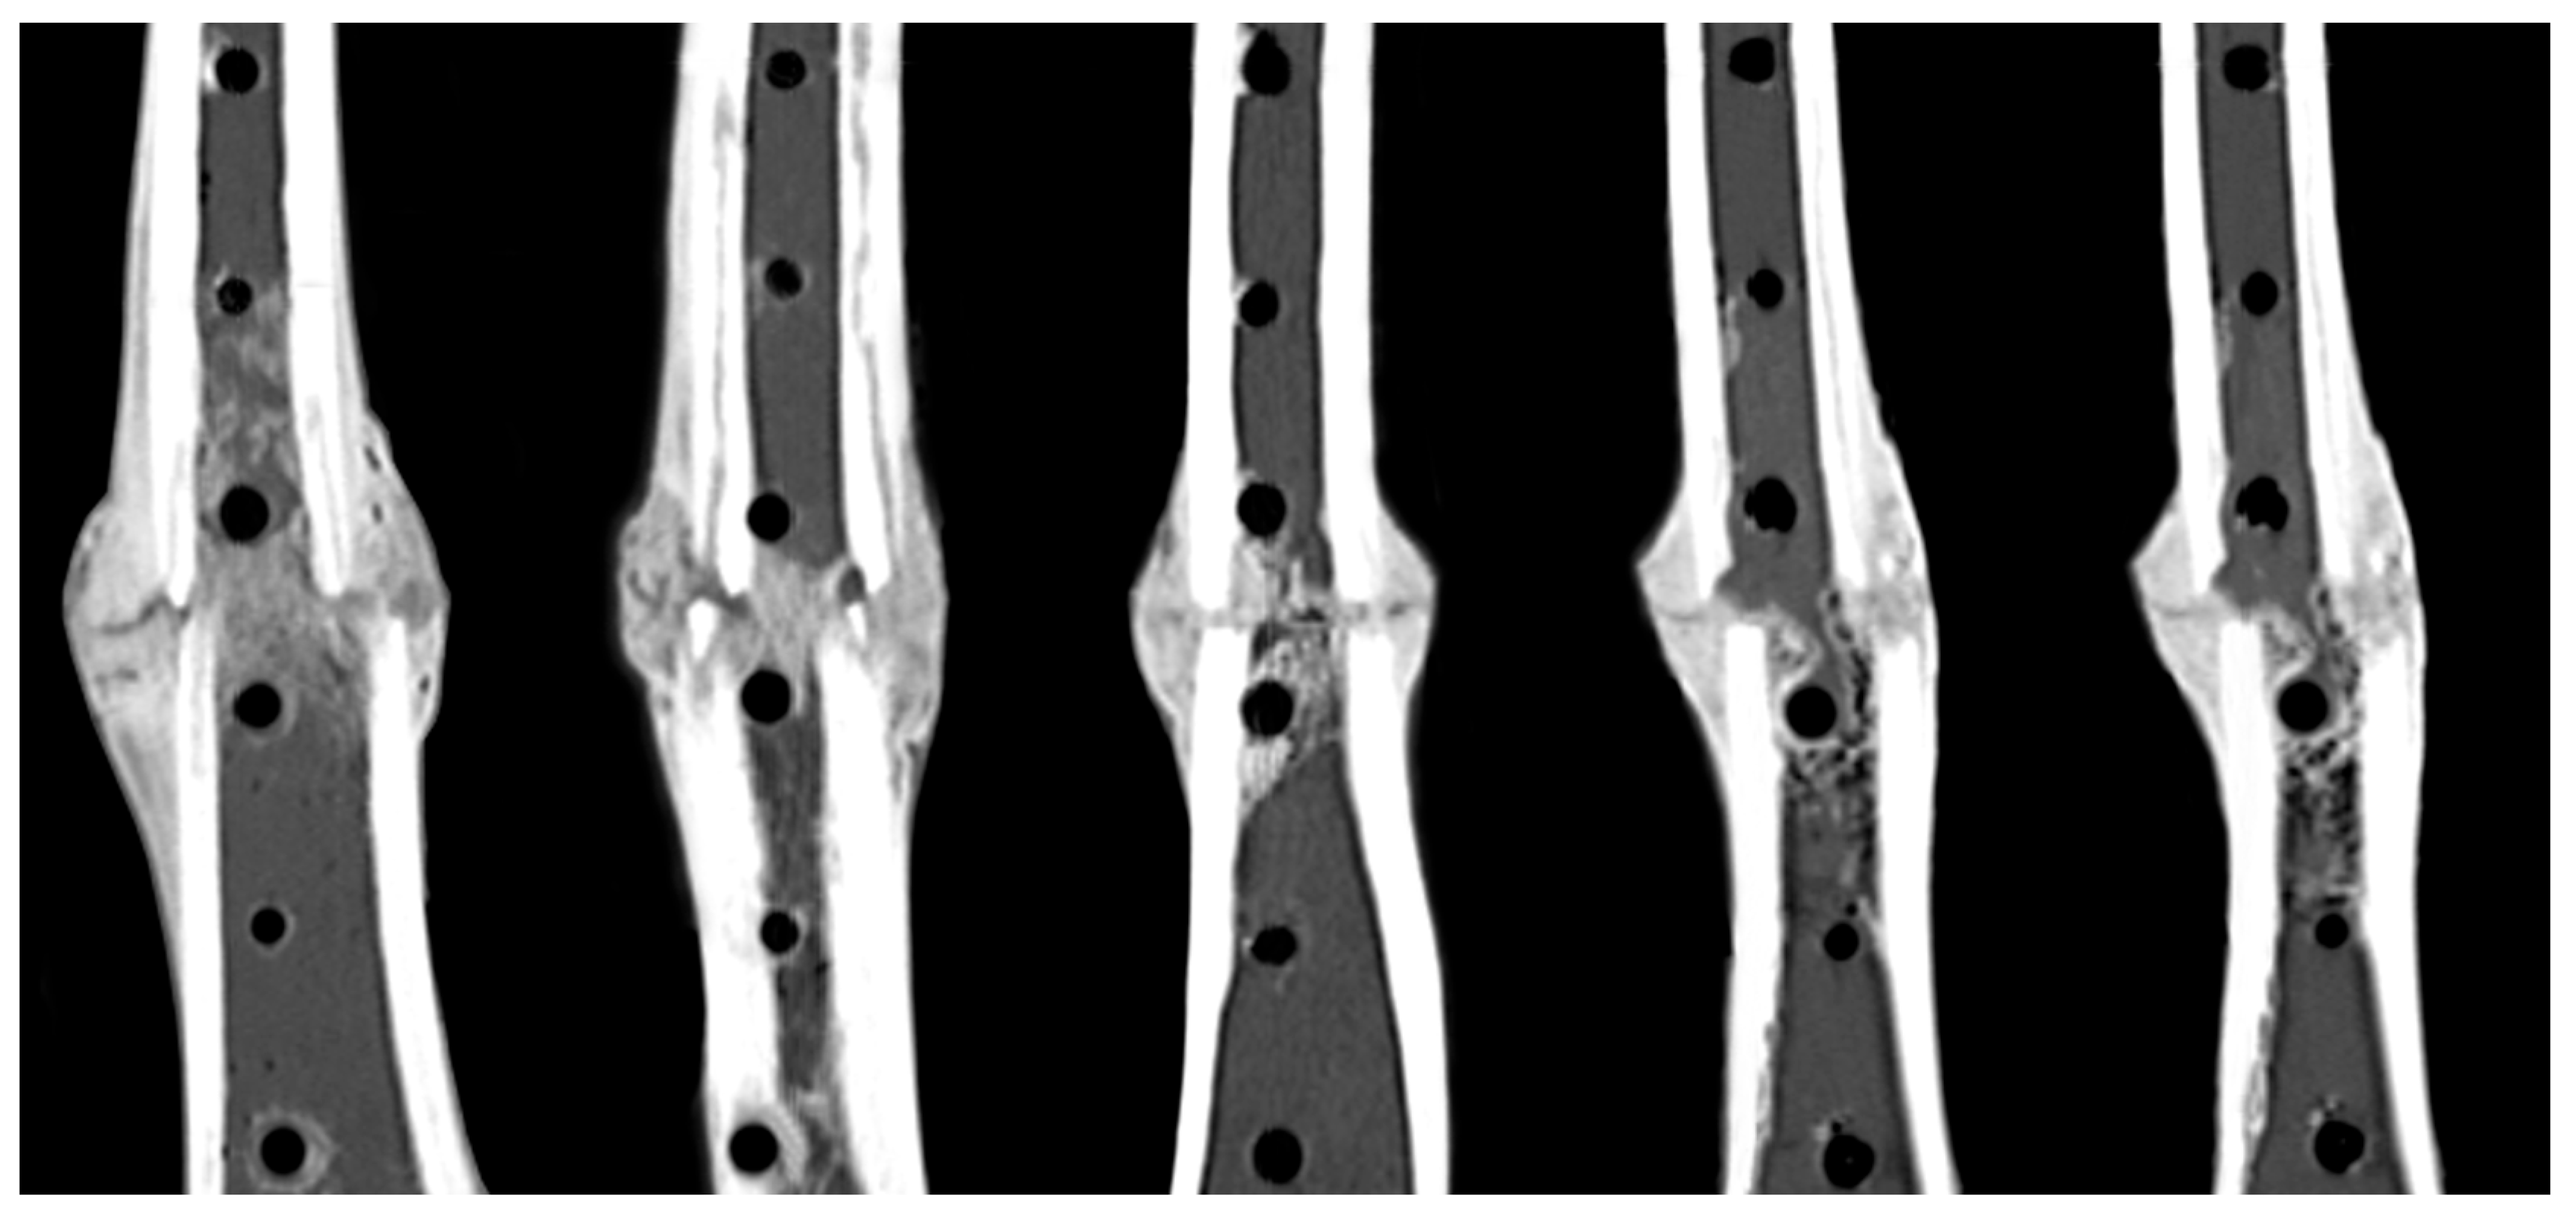

3.2. Healing Assessment